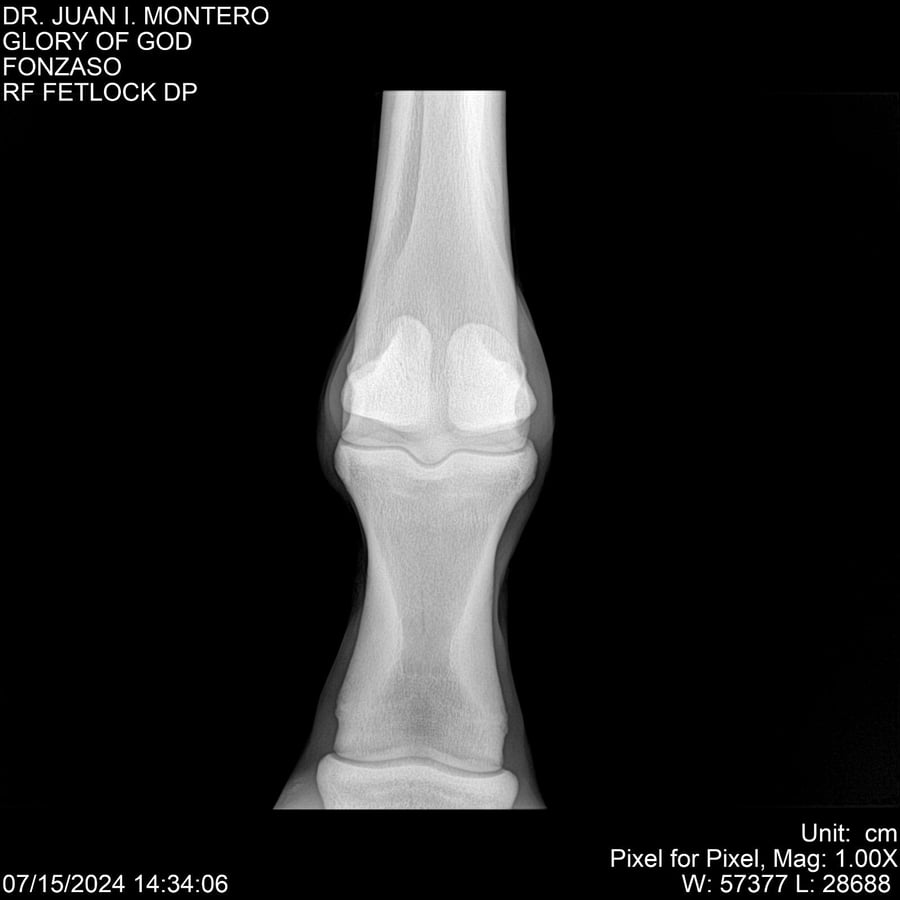

LOTE 10, GLORY OF GOD 🔥 🔥 🔥 Lote Anterior Volver al remate Lote Siguiente Ficha Contacto Montevideo - Ficha del Lote Identificador: #281389 Categoría: Yeguarizos Montevideo - 115 Visualizaciones ClicData Contacto Empresa: Abelenda N. R., Walter Hugo Nombre*: Teléfono* : E-mail* : Mensaje Enviar Registrese gratis Este contenido Exclusivo está disponible sólo para usuarios registrados Ingresar